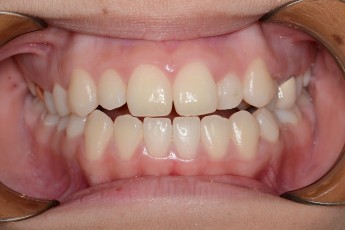

Before

After